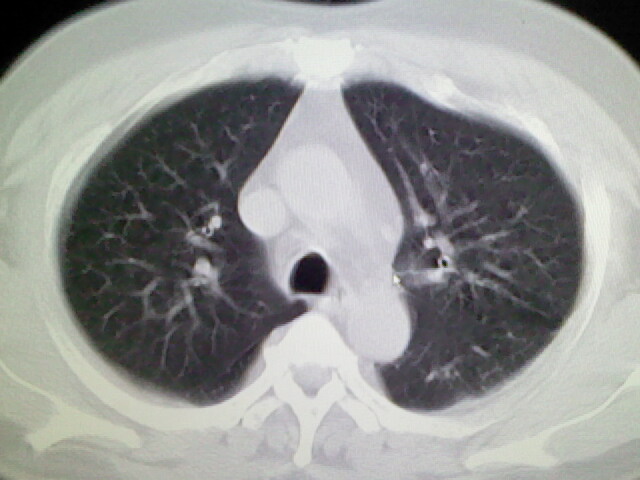

标题: CT17932:临床怀疑肺栓塞 [打印本页]

标题: CT17932:临床怀疑肺栓塞

男,34岁,自觉右侧胸痹,胸闷3天余

左上肺局限片状透光度增强区,肺纹理稀少,可考虑局限性肺气肿。

左上肺局限性肺透光度减低,肺纹理稀少;这虽然符合早期肺栓塞的改变,但与局限性肺气肿难以鉴别。

书上讲早期肺栓塞就是表现肺透光度减低,肺纹稀少。